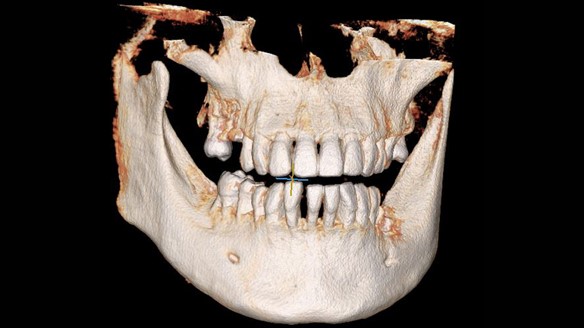

Өвдөлтгүй түргэн хугацаанд шинэ технологиор мэс ажилбарыг хийж байна. Имплант нь шүд байхгүй хэсэгт эрүүний ясанд унасан шүдний ёзоорын үүргийг гүйцэтгэдэг тусгай титанаар хийсэн эргийг суулган, эрүүний ястай бүрэн бэхжсэний дараа хиймэл цөгцийг холбон, өөрийн шүд шиг ашиглаж болох хиймэл шүдийг хэлнэ. Имплантын давуу тал нь энгийн хиймэл авагддаггүй, өөрийн шүдний 90% тай тэнцэх шүд учраас маш эвтэйхэн зовиургүй байдаг.

2020 онд манай ОРГИЛДЕНТ шүдний эмнэлгийн эмч нарын баг шүд шилжүүлэн суулгах мэс ажилбарыг 11 хүнд амжилттай хийлээ . Таны араа шүд хэрвээ эмчилгээ авахгүй , авахуулах шаардлагатай байгаа бол шүдээ авахуулсны дараа хиймэл шүд хийлгэлгүйгээр өөрийн агт араа шүдийг ашиглан зажлах үйлээ хадгалан үлдэх боломжтой боллоо .